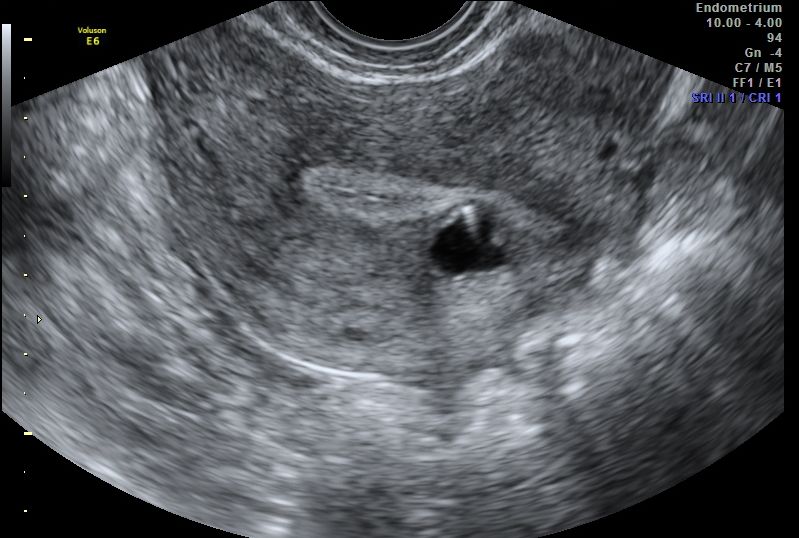

Hysteroscopy allows for the direct visualization of the uterine cavity, however its ability to diagnose adenomyosis is limited.